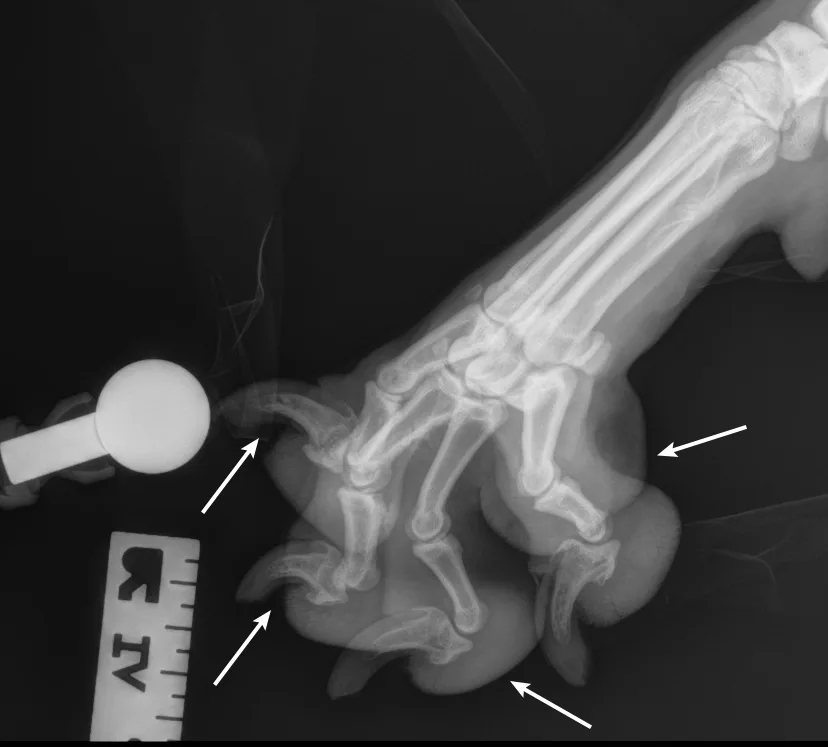

Place the patient in lateral recumbency with the affected limb on the table. Place a small object (eg, foam pad, gauze) under the calcaneus to keep the limb level and prevent overrotation of the limb and digits. Manually separate and tape down the digits (or use a wooden spoon to press, spread, and tape down the digits) to prevent to prevent superimposition on the radiograph—all digits should be visibly exposed and not overlap. Use a radiographic marker (eg, spherical ball marker, radiopaque numbered marker) to identify the different digits.

Step 2: Position the Beam

Center the collimator beam over the tarsometatarsal joints to include the distal metatarsals and all digits (the tarsus can also be included).

Author Insight

In these examples, the spherical marker ball was placed adjacent to digit V. Radiopaque numbered markers can also be used to individually identify each digit (not shown here). All digits should be separate and identifiable (arrows). The phalanges of each digit should be visible down through the toenail.